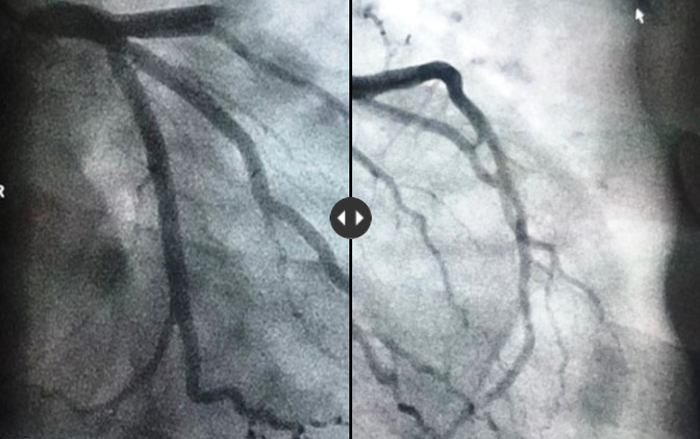

Kết quả chụp mạch vành cho thấy đoạn giữa động mạch vành bên phải của bệnh nhân bị tắc hoàn toàn. Bệnh nhân được hút huyết khối trong lòng động mạch vành và đặt stent tái thông đoạn mạch bị tắc. Sức khỏe ông cụ đang dần ổn định, dòng máu tại vị trí tắc nghẽn đã lưu thông bình thường trở lại.

Mạch vành trái của bệnh nhân bị tắc nghẽn…

Sau đó được tái thông.